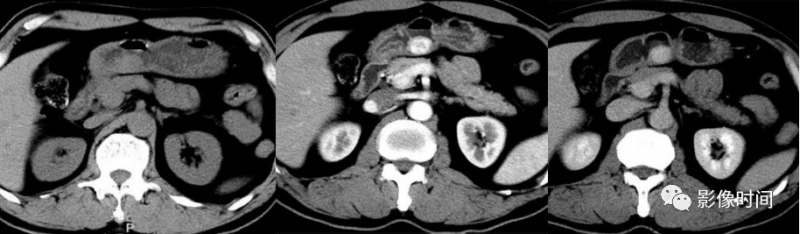

CT 体现:病灶坐落粘膜下,一般较小、单发,多坐落胃窦部,平扫为等密度,出血囊变稀有,偶见钙化,增强后动脉期呈显着强化,继续至门脉期。偶尔血管球瘤能够体现填充式强化。

血管球瘤,胃窦部粘膜下肿块,平扫呈均匀的等密度,增强后呈显着强化,门脉期仍呈高密度。

胃血管球瘤,CT 增强示胃窦部粘膜下肿块,向腔外成长,动脉期呈边际结节样强化,门脉期向中心填充。